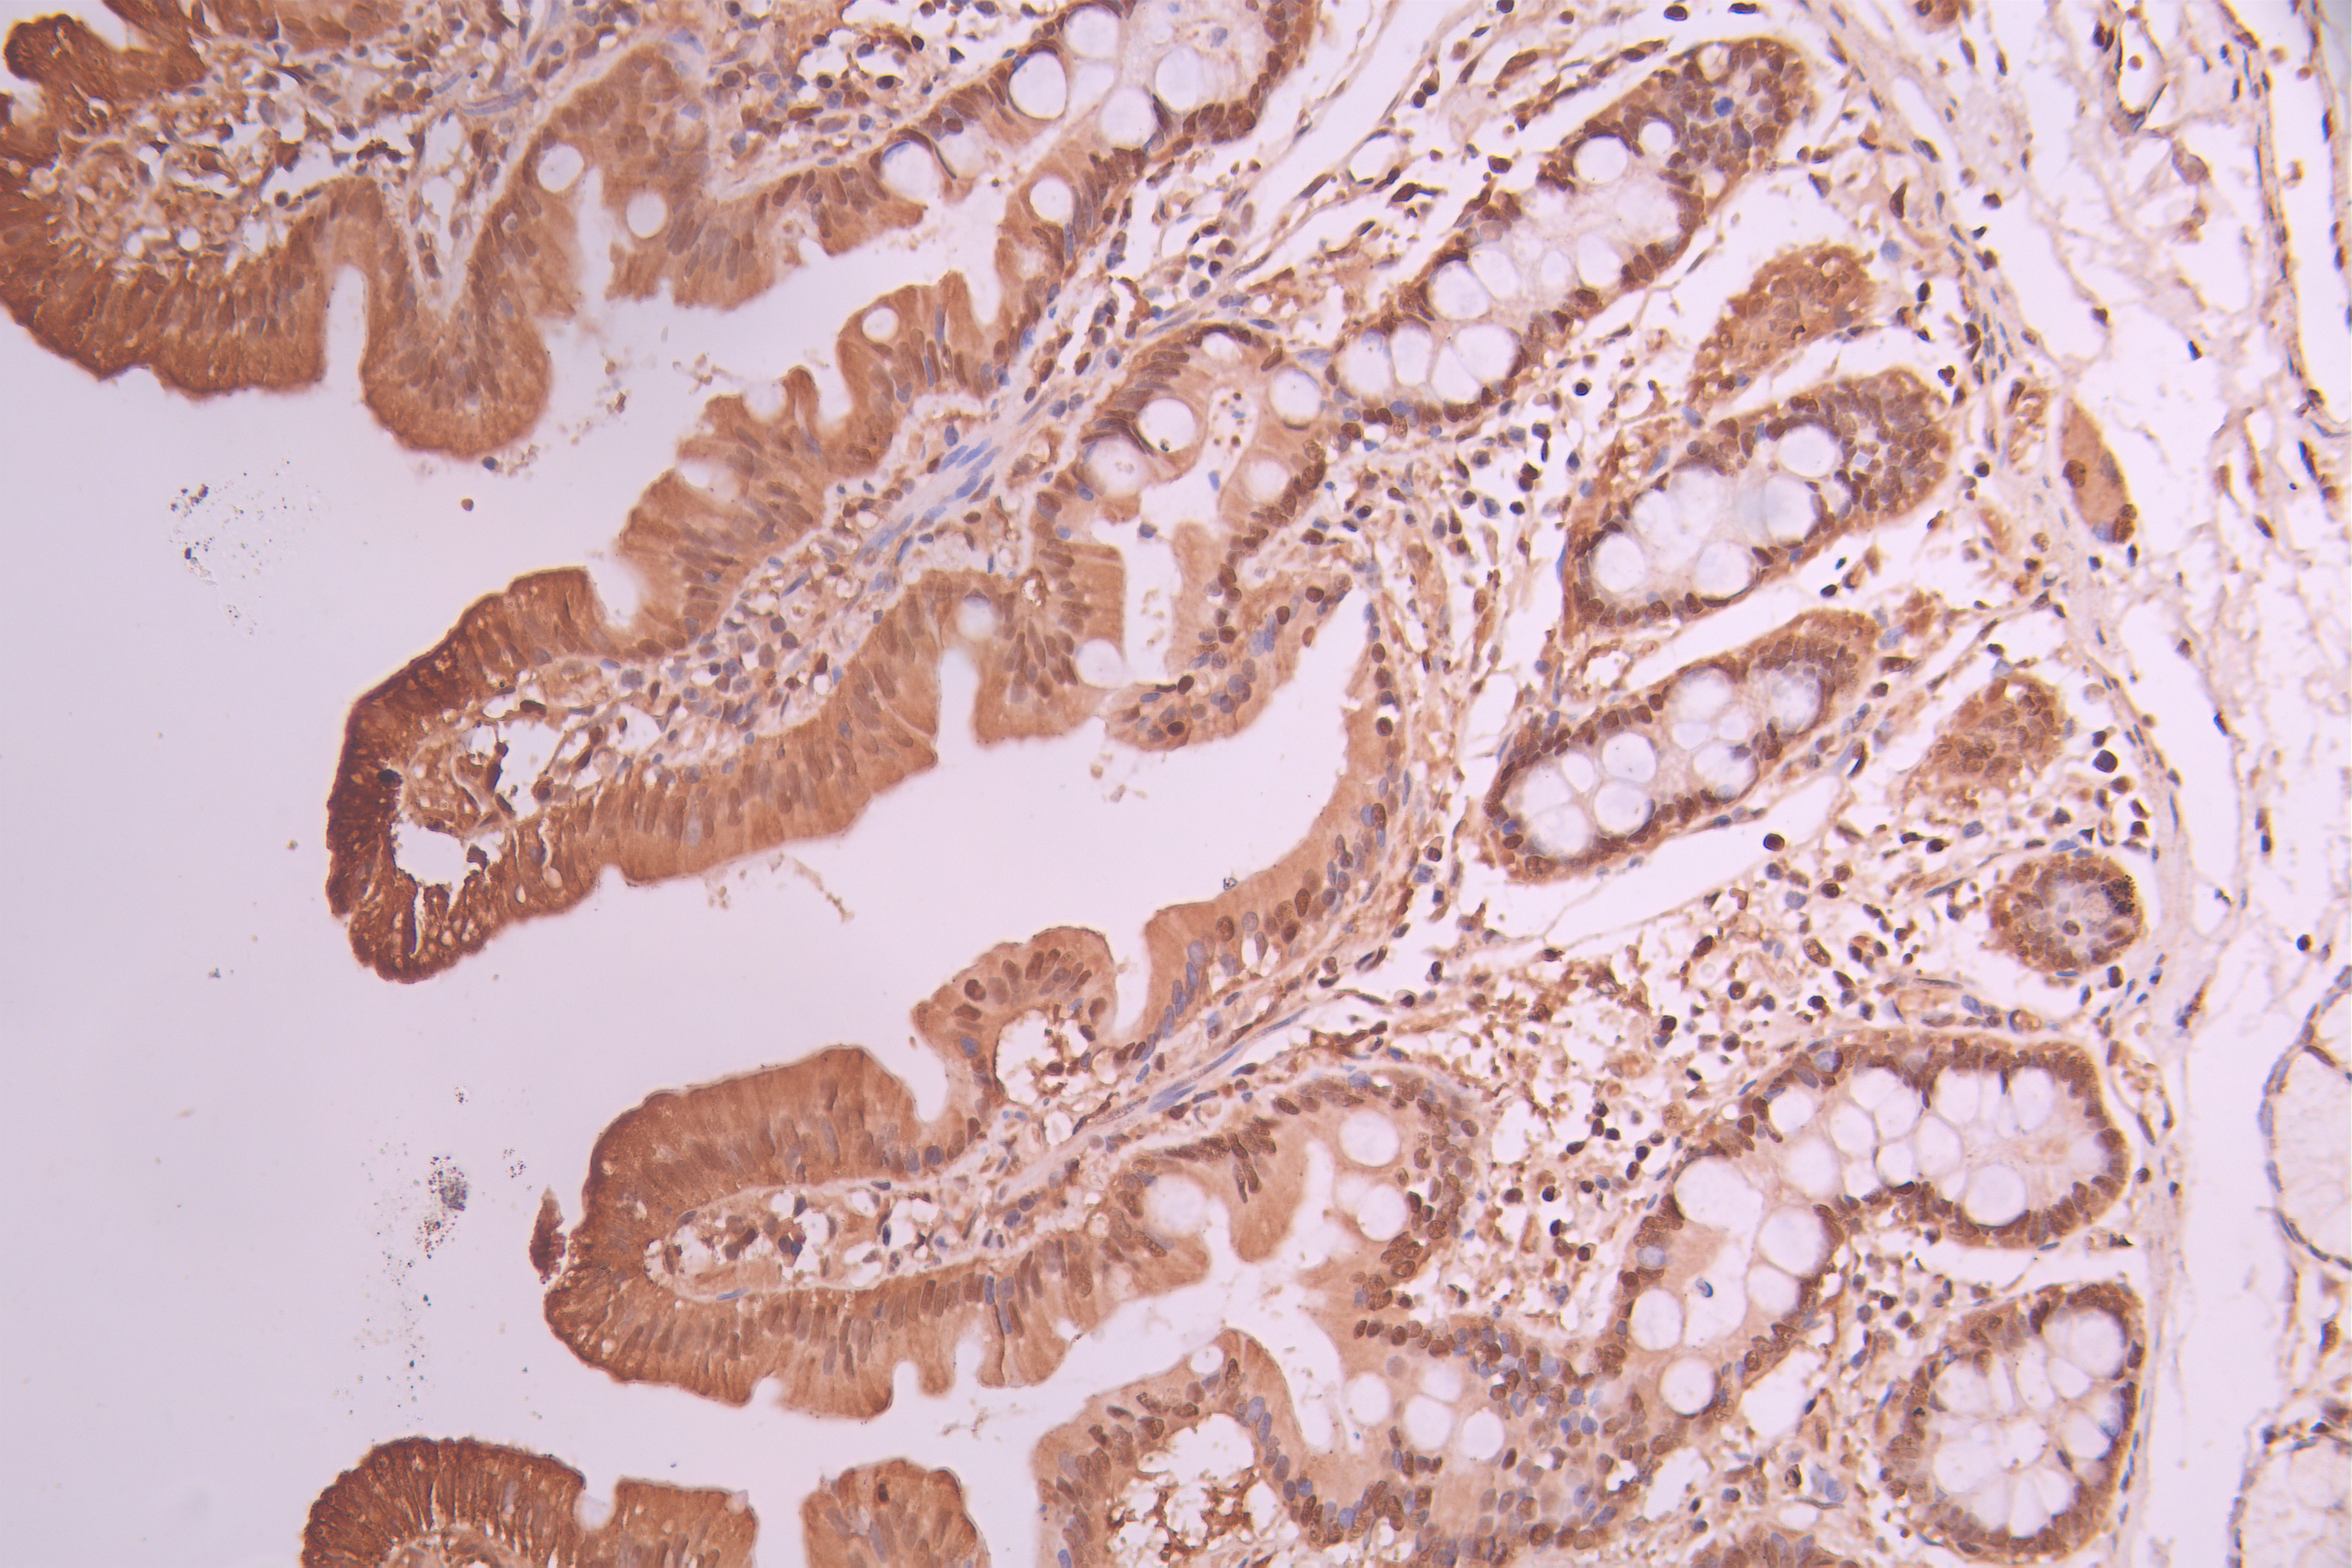

• IHC image of CSB-RA276081A0HU diluted at 1:100 and staining in paraffin-embedded human small intestine tissue performed on a Leica BondTM system. After dewaxing and hydration, antigen retrieval was mediated by high pressure in a citrate buffer (pH 6.0). Section was blocked with 10% normal goat serum 30min at RT. Then primary antibody (1% BSA) was incubated at 4°C overnight. The primary is detected by a Goat anti-rabbit polymer IgG labeled by HRP and visualized using 0.05% DAB.